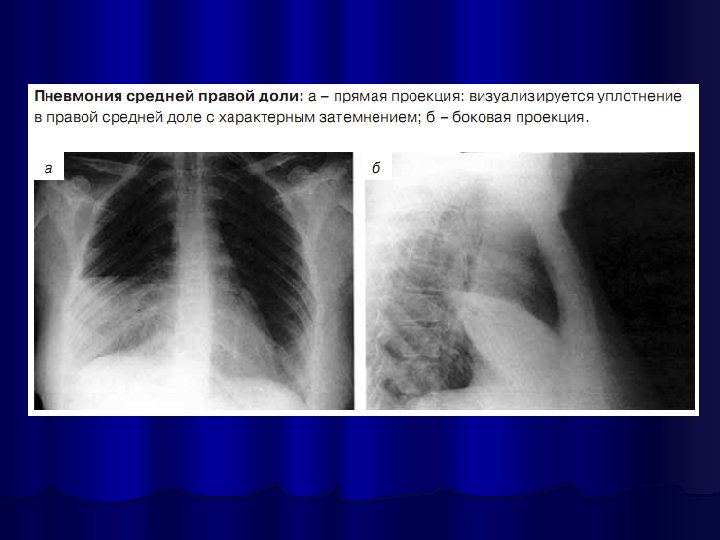

Рентгенография органов грудной клетки l обязательный метод исследования при пневмонии, l позволяет визуализировать пневмонический инфильтрат, l оценить динамику процесса, l распространённость инфильтрации, наличие плеврального выпота, признаков деструкции лёгочной ткани отражают тяжесть заболевания и определяют тактику лечения.

Рентгенологическое исследование проводится в начале заболевания и не ранее чем через 14 дней после начала АБТ; может быть выполнено и в более ранние сроки при возникновении осложнений или существенном изменении клинической картины заболевания l в практической работе полноформатная пленочная рентгенография часто заменяется крупнокадровой флюорографией или цифровой флюорографией, которая в этих случаях выполняется в аналогичных проекциях l в типичных случаях ВБП критерий диагноза - обнаружение очагово-инфильтративных или интерстициальных изменений в легких l

Правосторонняя верхнедолевая пневмония

ОБЯЗАТЕЛЬНО В ДИАГНОСТИКЕ ПНЕВМОНИИ: 2 проекции!!!